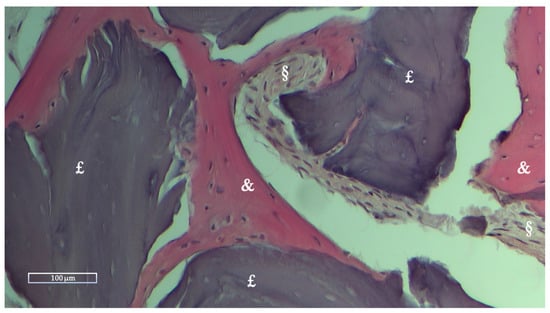

Histologic and Histomorphometric Results

| NFB | RB | SF | |

|---|---|---|---|

| Mean % ± Std dev | 28.27 ± 10.62 | 10.39 ± 12.01 | 61.33 ± 12.08 |

| Range % (Min-Max) | 16.51–59.74 | 0–36.89 | 40.26–75.59 |